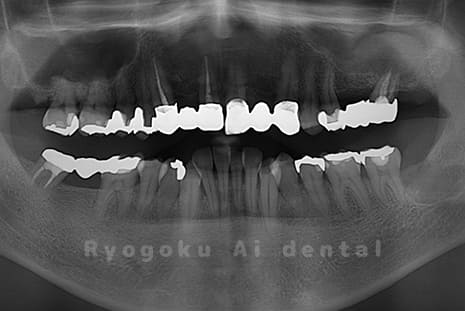

Case03

-

- 原因

- 上顎、下顎の親知らず

- 治療内容

- 上下4本の親知らずを抜歯したケースです。

<リスク・副作用>

手術後は痛み、腫れ、痺れなどの副作用が生じる場合があります。